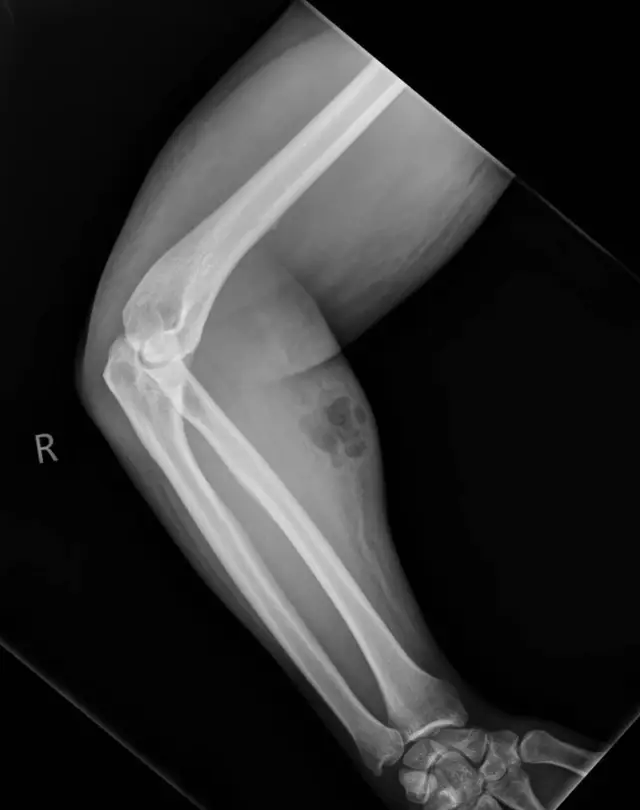

Doctors discovered a buildup of semen under his skin and signs of infection. Imaging tests showed trapped air in the tissue, a rare condition known as subcutaneous emphysema. He required urgent antibiotic treatment.